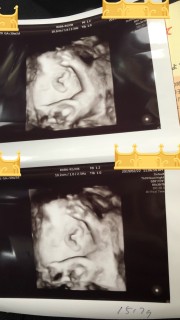

2週間で300g増えて1517gで標準だねと言われました。 逆子も直ってて2人目なので回ったのがすぐ分かりました。 そろそろ狭くなってきて定置する時期かな?と思ったらそうだと言われました。笑 顔は隠してたけどその仕草も可愛かったです。 姉妹予定でお姉ちゃんはニコニコしながらお腹(でべそ笑)触ってて微笑ましいです。 会わせるのが楽しみです。

1760gのハーフの男の子です★少し大きめみたいですが、個性の範囲内と言われました(o^^o)また逆子になってしまいましたが、久々に顔がちゃんと見えてパパ泣いてました♪♪可愛いすぎて早く会いたいです!